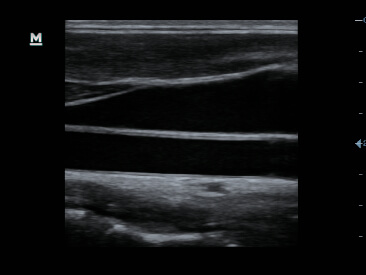

Clinical Images